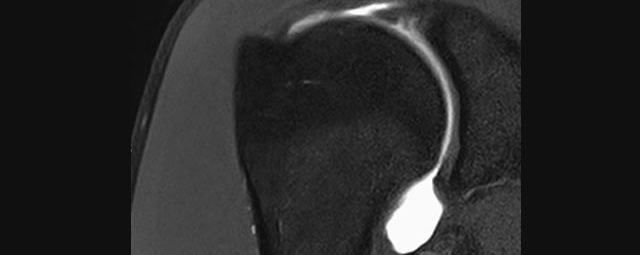

- Beurteilung von Knochen, Bändern und anderen Weichteilstrukturen der Gelenke nach Unfall.

- Impingement-Symptomatik

- MR-Arthrographie – nach örtlicher Betäubung und gründlicher Desinfektion der Haut wird unter Lagekontrolle mit Röntgen-Durchleuchtung eine kleine Nadel in den Gelenkraum positoniert und darüber ein MR-taugliches Kontrastmittel in den Gelenkraum gespritzt. Danach wird die Nadel entfernt. Anschließend erfolgt die MRT des Gelenkes. Diese Methode stellt kleine anatomische Strukturen des Gelenkraumes verbessert dar, z.B. zur Therapieplanung vor Arthroskopie bei Sportverletzungen der Schulter oder Gelenkinstabilität.